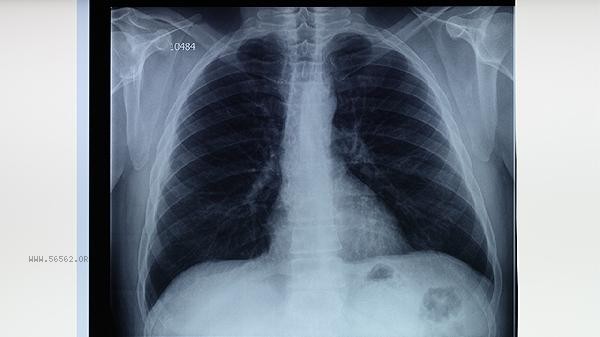

Old pulmonary tuberculosis refers to fibrotic and calcified lesions left over from previous infection with Mycobacterium tuberculosis after treatment or self-healing. This type of patient's lung imaging often shows linear shadows or calcifications, but sputum tests are negative and there are no symptoms of tuberculosis activity such as cough or low-grade fever. For routine entry physical examination or health certificate application, if the chest X-ray only indicates old lesions and there is no risk of infection, the physical examination institution usually approves it. Some special occupational medical examinations, such as pilots and divers, have high requirements for lung function and require comprehensive evaluation based on the results of lung ventilation function tests. When the scope of old lesions is large and leads to extensive fibrosis of lung tissue, it may cause a decrease in lung capacity or diffuse dysfunction, which may affect the physical examination items that have strict requirements for cardiopulmonary function. If the chest X-ray shows blurry edges of the lesion with surrounding infiltration shadows, or if acid fast bacilli are detected in the sputum smear, it indicates tuberculosis recurrence and treatment is needed. At this time, the physical examination will not pass. Some medical institutions may require previous tuberculosis treatment records and recent follow-up reports to exclude active tuberculosis.